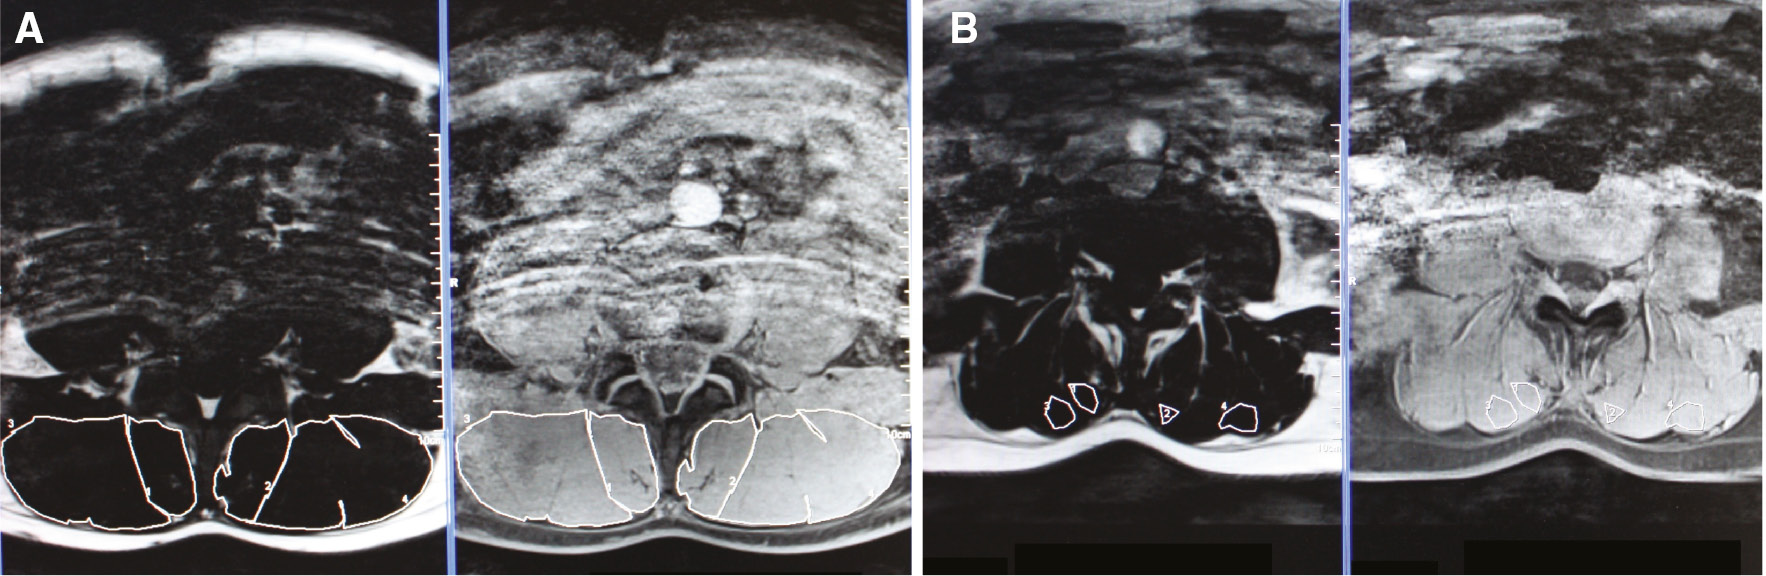

To estimate the total CSA of ES and MF, the region of interest (ROI) was outlined in the fat image, which was automatically copied onto the water image (Fig. 1A). ES and MF were outlined in two slices, at the height of L4, since measurements at L4 seem surrogates for the complete lumbar spine [41]. The total CSA of each muscle was calculated as the number of voxels in the respective ROI, multiplied by voxel size. A mean value of both slices was calculated, respectively for right and left ES and MF.

(A) Provides the ROI of the complete left and right ES and MF. (B) Provides the ROI for MFI in the left and right ES and MF. Therefore, an area with lean muscle tissue was selected.

To estimate the amount of fat in lean muscle tissue (lean MFI), the fat index in homogenous muscle tissue was estimated (Fig. 1B). Therefore, the procedure above was repeated, but in a homogenous muscle region instead of the total muscle region.